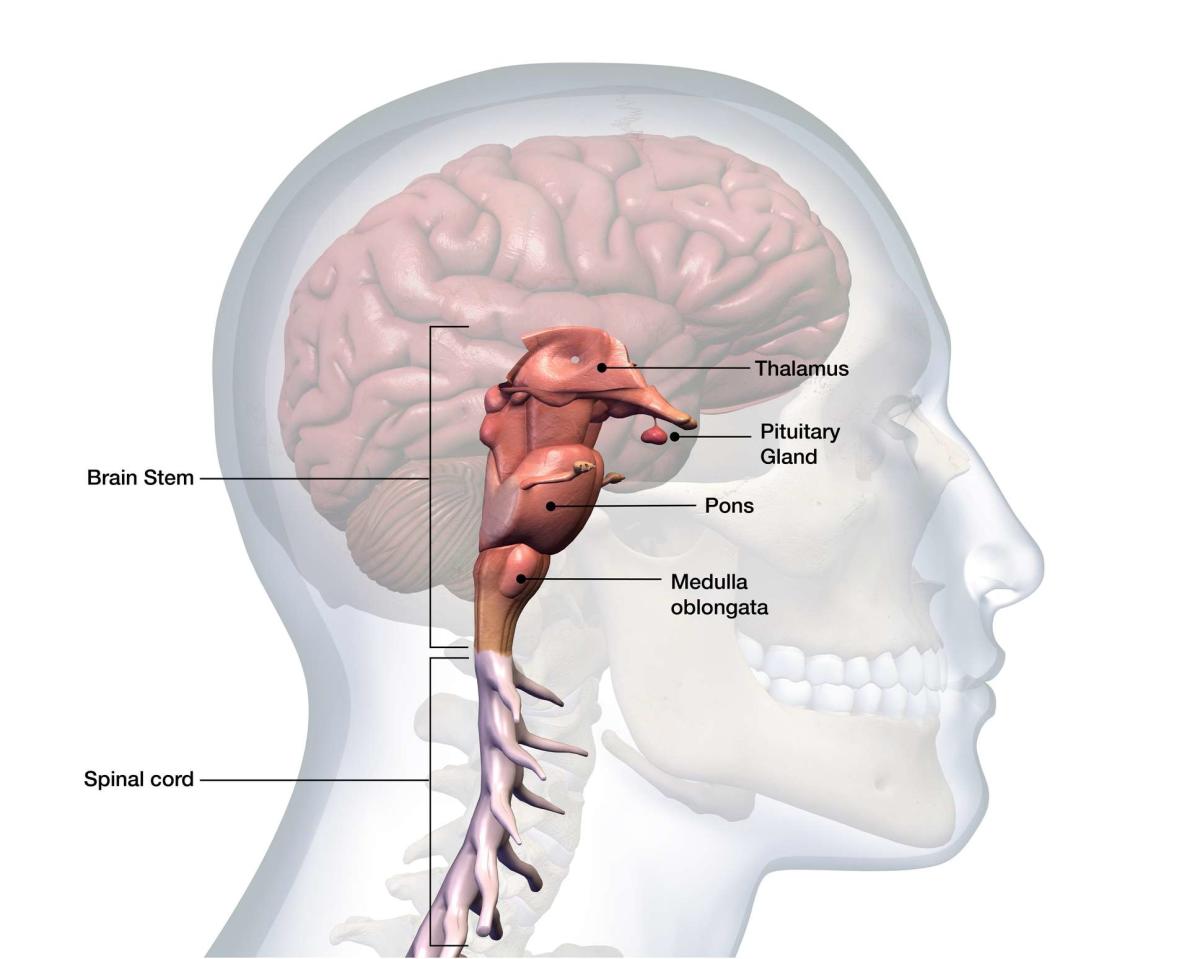

Medulla Oblongata: What It Is, Function & Anatomy

The Anatomy of the Medulla Oblongata

The Medulla Oblongata - Internal Structure - Vasculature

Medulla Oblongata vs. Pons | Locations, Functions & Structures Video

The Medulla Oblongata and Pons

Surgical Anatomy of the Medulla Oblongata | SpringerLink